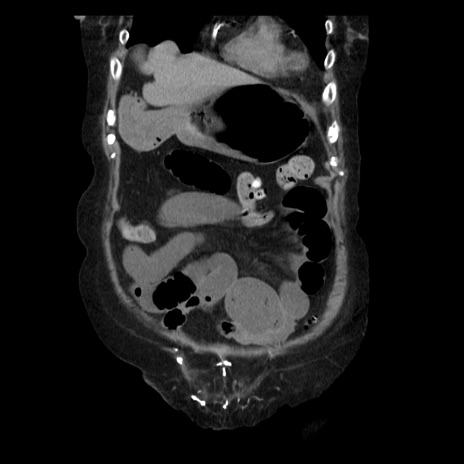

症例14(冠状断像)

【症例】 90歳代女性

【主訴】 腹痛・嘔吐

【現病歴】今朝から左側腹部痛を認めた。 経過観察していたが、嘔吐を認めたため来院。

【既往歴】 子宮癌術後

【身体所見】 意識清明、BP 127/54mmHg、P 98bpm Sp02 95%(RA)、BT 35.8°C、腹部平坦・軟腸ぜん動音聴取良好、右下腹部圧痛(+) 反跳痛なし

【データ】WBC 9800、CRP 0.46